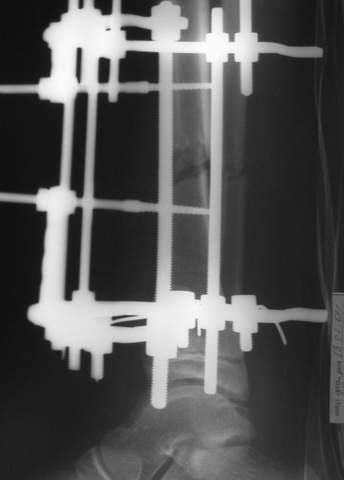

2

3a

3b

В аттачте № 3 - один из примеров полукольцевого аппарат...

Это уже я баловался.

Итог? Работы больше (по времени и

интраоп "подгонке"), срастается также, а особого преимущества по сравнению с

"чиста" кольцевым (вес, удобство ношения и пр.) - я, по крайней мере,

не нашел.

Теперь не балуюсь.